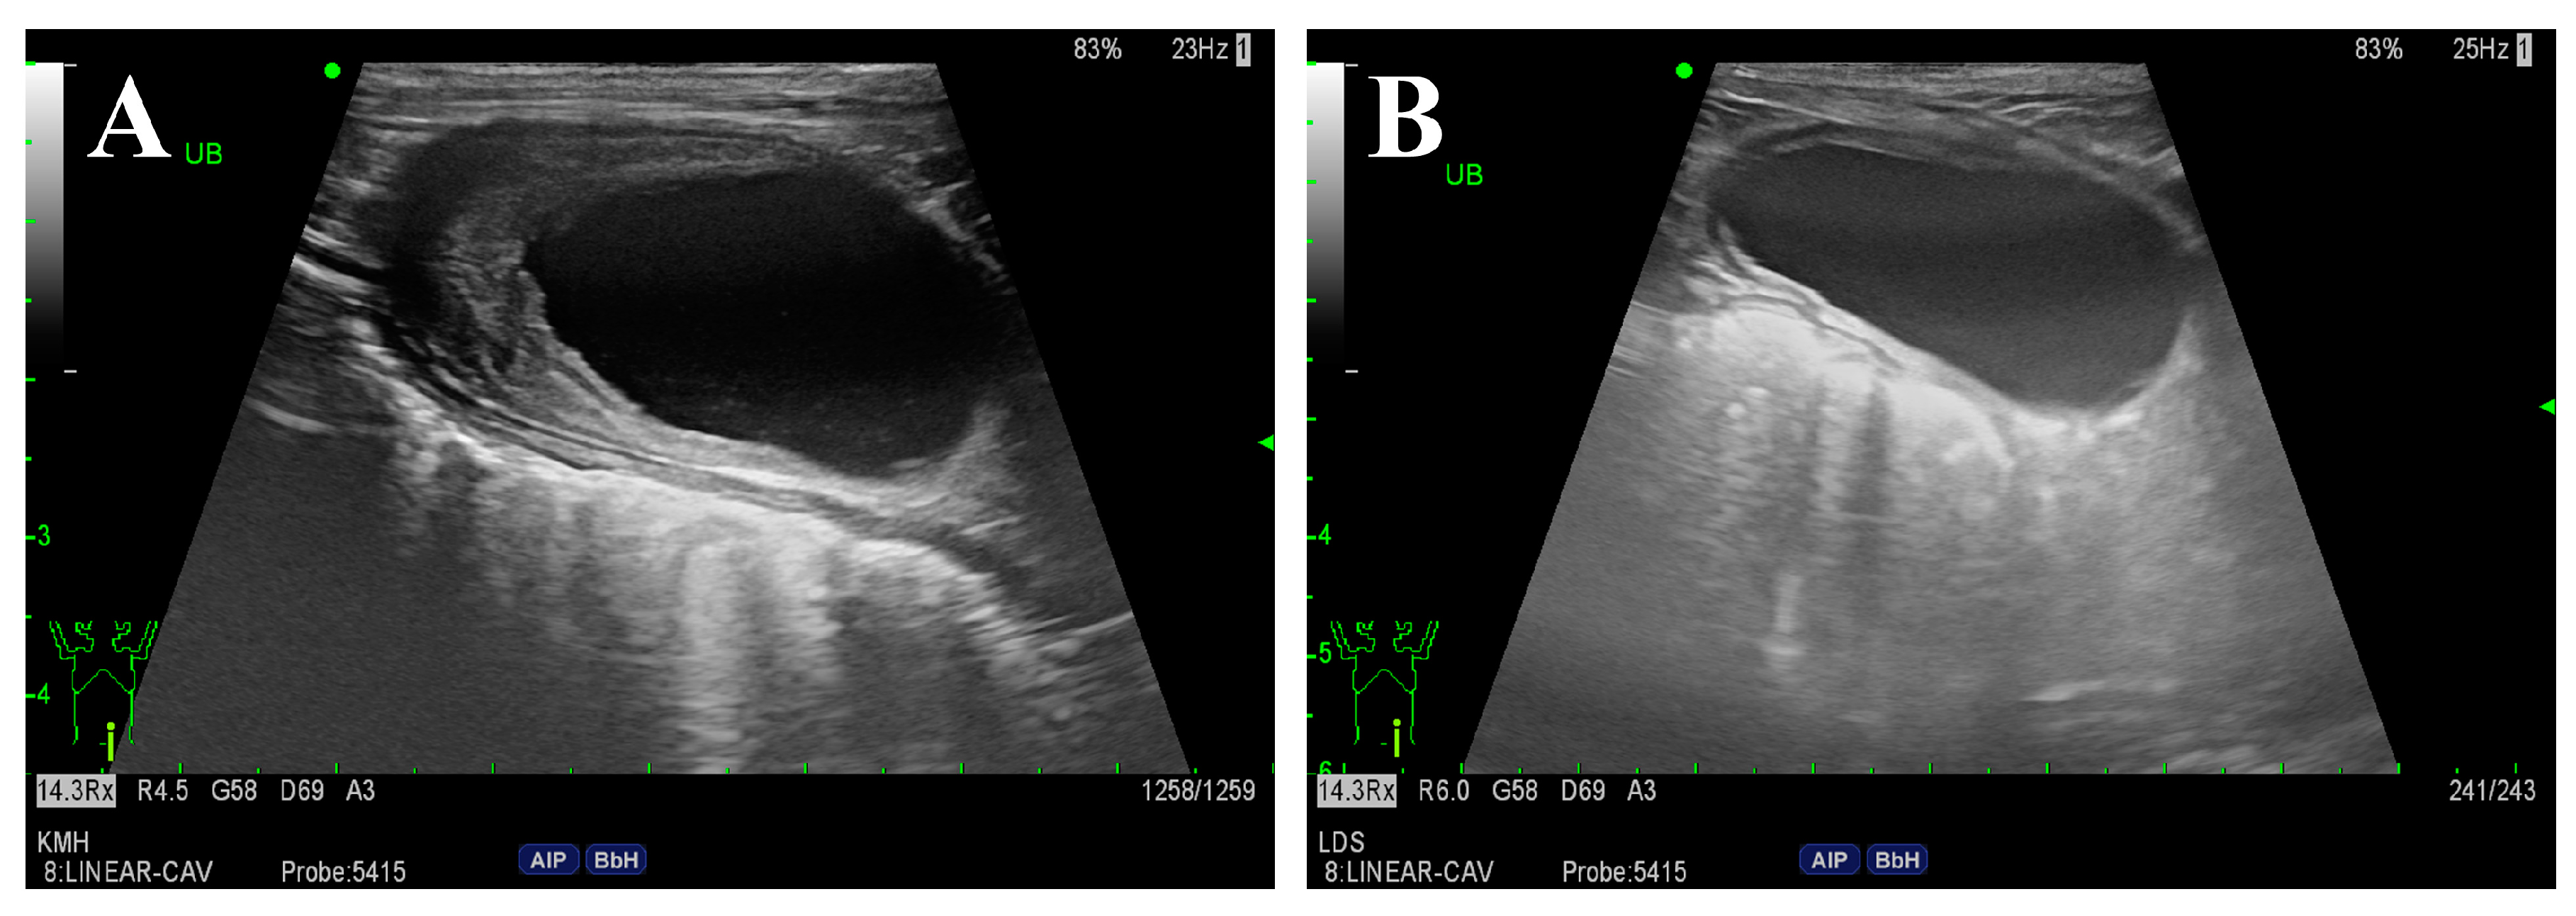

2. Case Description

3. Diagnostic Assessment, Intervention, and Outcomes